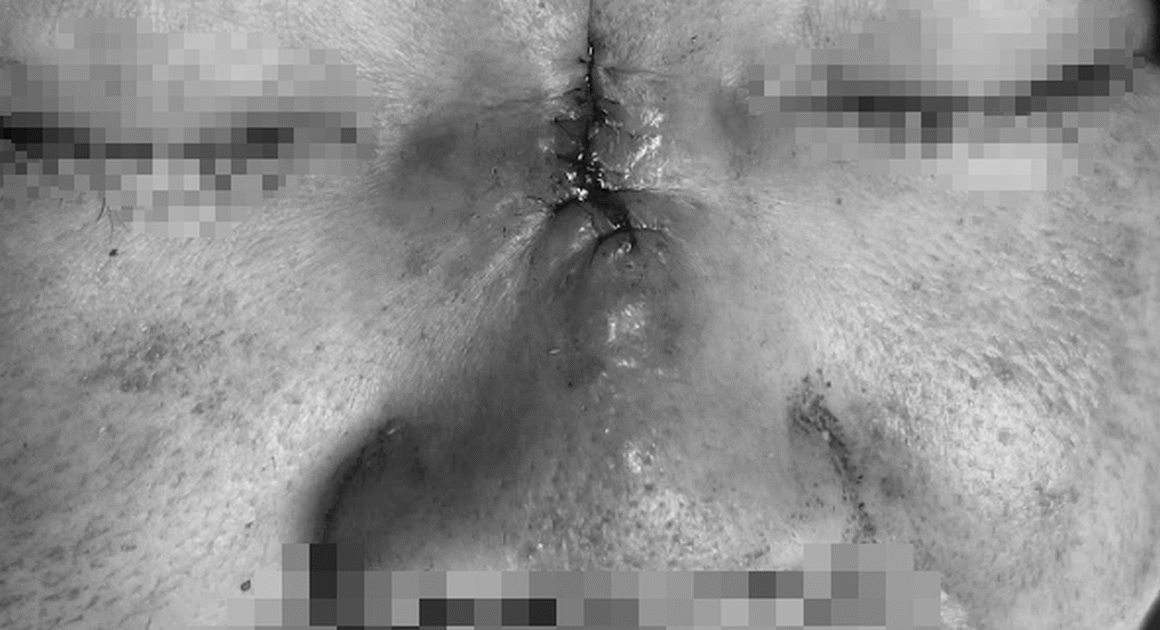

BỆNH NHÂN 43 TUỔI Ở LẠNG SƠN GẶP TÌNH HUỐNG NGHIÊM TRỌNG: MŨI HOẠI TỬ VÀ CÓ NGUY CƠ MẤT MẠNG!

CẢNH BÁO: NHỮNG HÀNH ĐỘNG NHIỄU LOAN SỨC KHỎE TỪ NHỮNG “THẦY PHONG THỦY” TRÁI PHÁP